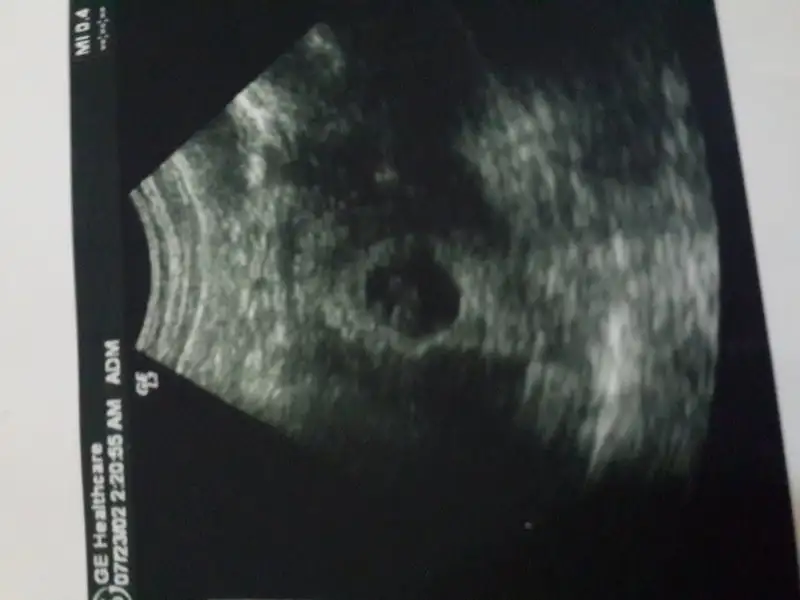

Cok sukur canim salı günü gördük. İyilermış çok sukur kipir kipirlardi :)Sağol canım Allah razı olsun sen naptin bebeklerini gördün mü

Maşallah canım ne güzel bende salı günü gördüm BebeğimiCok sukur canim salı günü gördük. İyilermış çok sukur kipir kipirlardi :)

Ay ne güzel haber ilk bebismi canımMerhaba kizlaaaarrrr :) bugun kontrole gittim ikili test yaptirdim, olculeri makuldu, kan verdim cmt cikicak insallah sonuclar. Ziplayip hoplayip duruyordu valla icim bi garip oldu :) kiza benziyor dedi ama 3-4 haftaya netlesir dedi

Bugün öğlen yemeğinden sonra kanamam oldu.soluğu hemen doktorda aldım. İlk önce usg ile baktı kalp atışı normal bebiş iyi ama kanaman var dedi.

Canim adet duzensizligin varmiydi?Iyi akşamlar arkadaşlar. Iki haftadır 3 farklı doktora gittim çünkü 9 haftalik olmasi gereken gebeliğim 6 haftalik olarak gorunuyo. Bir doktor çok geç dollenme olmus dedi. diğeri iki hafta sonra gel dedi başka bi açıklama yapmadı diğer doktor da ya geç dollenme olmuştur ya da dillendirmek istemiyorum ama bebek gelisememis olabilir dedi. Crinone jel verdi. Zaten kan pihtilasmasi yüzünden iki kez düşük yaşadım. Şu an igne de kullaniyorum kan sulandirici ama çok tedirgin oldum. Sizin de var mı bildiğiniz bu şekilde çok geç dollenme yaşayıp sonradan bebeğini doğuran ya da kalp atışını duyan

Gec dollenmedir cnm ya . Kalp atisi duyldu muIyi akşamlar arkadaşlar. Iki haftadır 3 farklı doktora gittim çünkü 9 haftalik olmasi gereken gebeliğim 6 haftalik olarak gorunuyo. Bir doktor çok geç dollenme olmus dedi. diğeri iki hafta sonra gel dedi başka bi açıklama yapmadı diğer doktor da ya geç dollenme olmuştur ya da dillendirmek istemiyorum ama bebek gelisememis olabilir dedi. Crinone jel verdi. Zaten kan pihtilasmasi yüzünden iki kez düşük yaşadım. Şu an igne de kullaniyorum kan sulandirici ama çok tedirgin oldum. Sizin de var mı bildiğiniz bu şekilde çok geç dollenme yaşayıp sonradan bebeğini doğuran ya da kalp atışını duyan